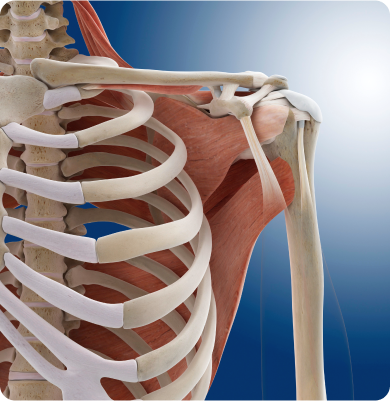

오십견

어깨 관절을 둘러싼 관절막이 퇴행성 변화를 일으키면서 염증을 유발하는 질환

주요원인

주로 40~60대에 발생하며 어깨를 오래 사용하지 않거나 움직임이 제한될 때 관절이 굳어 생기거나 당뇨병 등 기저질환이 원인이 됩니다.

주요증상

• 어깨 쪽에 둔한 통증이 시작되다 서서히 통증이 심해지면서 관절 운동이 제한됩니다.

• 누워있는 자세에서 통증 및 불편함이 심해져 수면 장애가 발생합니다.

• 관절 운동은 모든 방향에서 제한되며 일상생활이 크게 불편해 집니다.